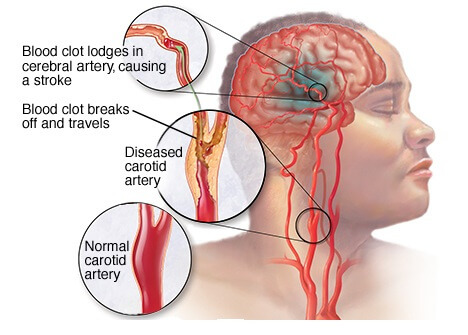

Overview

Package includes:

Days in hospital : 3 to 4 Days (For patient and one attendant)

Days in hotel : 8 Days (For patient and one attendant)

Room type in hospital : Shared

Room type in hotel : Private

Hotel category: Standard

Value added benefits of the Minimally Invasive Surgery with Carotid Endarterectomy:

Ø Doctor consultation charges

Ø Lab tests and diagnostic charges

Ø Room charges inside hospital during the procedure

Ø Surgeon Fee

Ø Nursing charges

Ø Hospital surgery suite charges

Ø Anesthesia charges

Ø Routine medicines and routine consumables (bandages, dressings etc.)

Ø Food and Beverages inside hospital stay for patient and one attendant.